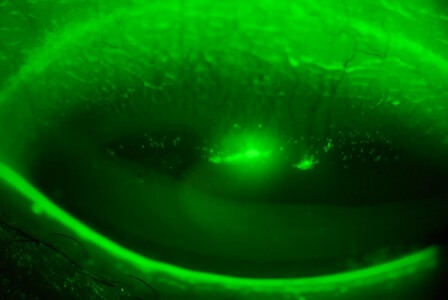

眼紅

照片由香港理工大學眼科視光學院提供

血管擴張

照片由香港理工大學眼科視光學院提供